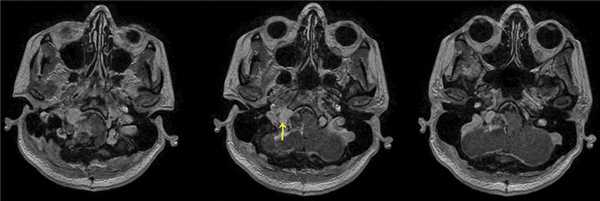

При проведении МРТ головного мозга пациентки В. на 3-и сутки после операции выявлена остаточная часть опухоли в канале подъязычного нерва (рис. 5). Рис. 5. МРТ головного мозга пациентки В. на 3-и сутки после операции. При усилении сигнала парамагнетиком определяется остаток опухоли в канале подъязычного нерва справа (указано стрелкой).

(Слева) При МРТ Т1 в аксиальной проекции наблюдается асимметрия сигнала языка. Правая половина языка не изменена; четко отграниченная левая половина языка дает патологически усиленный сигнал. Усиление сигнала свидетельствует о жировой инфильтрации и требует исследования канала подъязычного нерва.

(Справа) При МРТ Т1 с КУ в аксиальной проекции определяется дольчатое объемное образование левого подъязычного канала, распространяющееся в цистерну продолговатого мозга. Обратите внимание на отсутствие изменений правого канала подъязычного нерва. Отмечается равномерное контрастирование объемного образования, что характерно для шванномы. В ткани крупных опухолей часто наблюдаются кистозные изменения.

3. МРТ при шванноме подъязычного нерва:

• Т1 ВИ МРТ:

о Как правило, изоинтенсивна по сравнению с серым веществом

о Сопутствующая денервация может вызывать атрофию мышечной ткани языка на стороне поражения и ее замещение жиром, что сопровождается усилением сигнала

• Т2 ВИ МРТ:

о Как правило, усиление сигнала

о Крупные ШПН могут содержать интрамуральные кисты с усилением Т2-сигнала

• Т1 ВИ МРТ с КУ:

о Наблюдается однородное контрастирование мелких опухолей